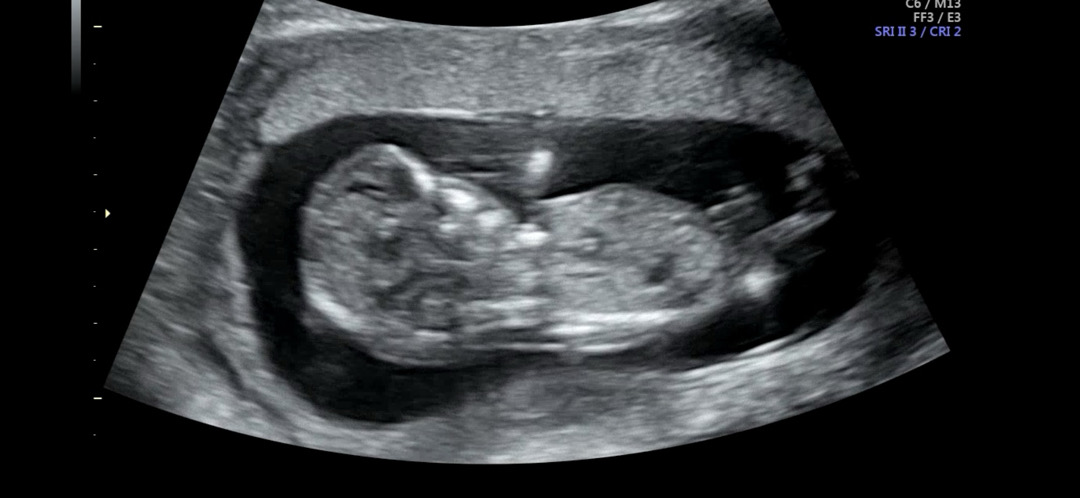

각도법 봐주세용 ..! ㅠㅠ

12주에 본 초음파에요ㅠㅠ! 너무너무 궁금해서 올려봅니당! 아무리 봐도 감이 안잡히는 초보 엄빠랍니다! 마구마구 알려주시면 감사해용❣️ (각도법 문의 게시물 불편하신 분들껜 죄송합니당..!)

아들이요!

아들 인 것 같은데용??